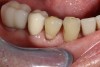

CAD/CAM dentistry is very precise. For accuracy, the preoperative, shade, bite, and upper/lower tooth scans are best taken before anesthesia and dental procedures that induce muscle fatigue (Figure 3). After infiltration anesthesia with 1 carpule of articaine hydrochloride 4% and epinephrine 1:100,000 injection, the temporary was removed. Occlusal reduction of 2.0 mm was precise and defined with an 828Y depth cutting bur to meet restorative requirements (Figure 4), and the post space was restored. Axial reduction and shoulder margination were performed with a coarse KS1 bur. After smoothing of the preparation, a 15% aluminum chloride topical gingival retraction paste was injected and compressed into the sulcus, then thoroughly rinsed with water and air-dried, before scanning of the tooth preparation and critical adjacent anatomy (Figure 5 and Figure 6).

Fig 3. Digital bite restorations are best scanned before anesthesia and restorative care.

Figure 3